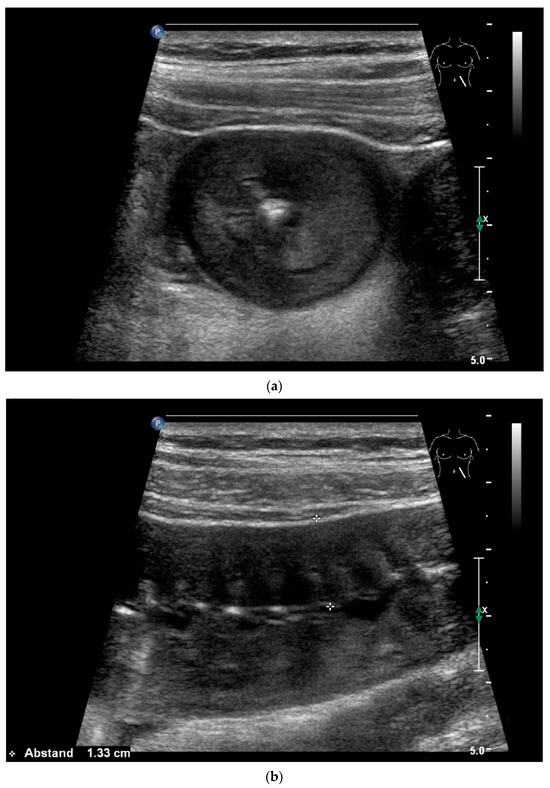

Figure 10.

Diffuse large B-cell lymphoma (DLBCL). In the right mid-lower abdomen, a large, smoothly circumscribed mass is present around the ileum (“pseudo kidney sign” (a)). Using a high-resolution linear transducer, the mass appears smoothly circumscribed and almost anechoic (b). The ileum runs centrally, and the echogenic wall is clearly defined (c). This wall does not merge into the mass. Since the mass is almost anechoic, it is also difficult in different transducer positions to distinguish whether it is a liquid lesion or a solid mass (b,c). CEUS with 2.4 mL SonoVue (9 MHz linear transducer) shows homogeneous arterial enhancement (d), but the intensity decreases with time in the venous phase (e). The ileal wall enhancement centrally within the mass is more intense than that of the tumor (d,e).